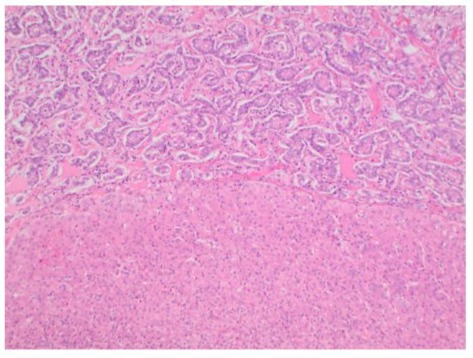

Case

Figure 3: Microscopic appearance of the tumoral lesion (T) in the resected liver specimen compared to normal liver tissue bed (N). The architectural pattern is trabecular and glandular with nested cells. H&E x 100.

PHNET is a very rare tumor, and it requires strict exclusion from other more common hepatic malignancies such as carcinoid metastasis, cholangiocarcinoma, hepatic adenoma, and hepatocellular carcinoma [7,8]. Diagnosis is primarily made with immunohistochemistry and radiological exclusion of metastatic disease from gastrointestinal or systemic origin. Imaging guided diagnosis such as octreotide scintigraphy (OctreotrideScan) and Ga-68 Dotatate PET-CT scan have been used in the preoperative and postoperative settings to identify primary location of the tumor [9]. To date, there are no specific imaging guidelines to diagnose PHNET which makes it very difficult to make an accurate diagnosis without analyzing the surgical specimen [9]. The high lesion to background resolution of Ga-68 Dotatate PET-CT scan make it a very sensitive tool to rule in the diagnosis of PHNET as it identifies any extrahepatic NETS or metastasis [9]. Utilization of this scan preoperatively is a way to identify lesions that can be surgically resected. Postoperatively, the test can be used to identify extrahepatic lesions and monitor recurrence [10]. Additionally, laboratory markers such as AFP, CEA, CA19-9 are not very helpful in diagnosis of PNHET as they are usually within normal limits. (lia-xing) Blood levels of chromogranin A or serotonin do not aid in differentiating PHNET from other forms neuroendocrine neoplasms. Pathological features of hepatic NETs generally appear macroscopically as brown to yellow-grey colored, well demarcated lesion with irregular hemorrhagic areas containing cystic components. (source) In our presented case, the tumor had cystic component on CT, and irregular bordered necrotic yellow mass on gross specimen. (Figure 2) Microscopic appearance of the tumor exhibits an insular, nested, trabecular or a mixed pattern of cell growth. (Figure 3) In literature, they are described to be positive for chromogranin A, CD 56 and synaptophysin A. (source everyone) Our findings are supported by this evidence. Cellular assessment of the tumor is an adequate tool to predict malignant potential of these tumors [11]. The 2019 WHO classification of NET consists of three grades (G1, G2 and G3) which are related to the mitotic index and ki-67 index: NET G1 presents, respectively <2 and < 3 %, NET G2 is 2-20 and 3-20 %, and NET G3 > 20 and >20 %, respectively [11,12]. In our presented case, the tumor had low - medium malignancy potential with Ki-67 of 3% placing it as a G2.